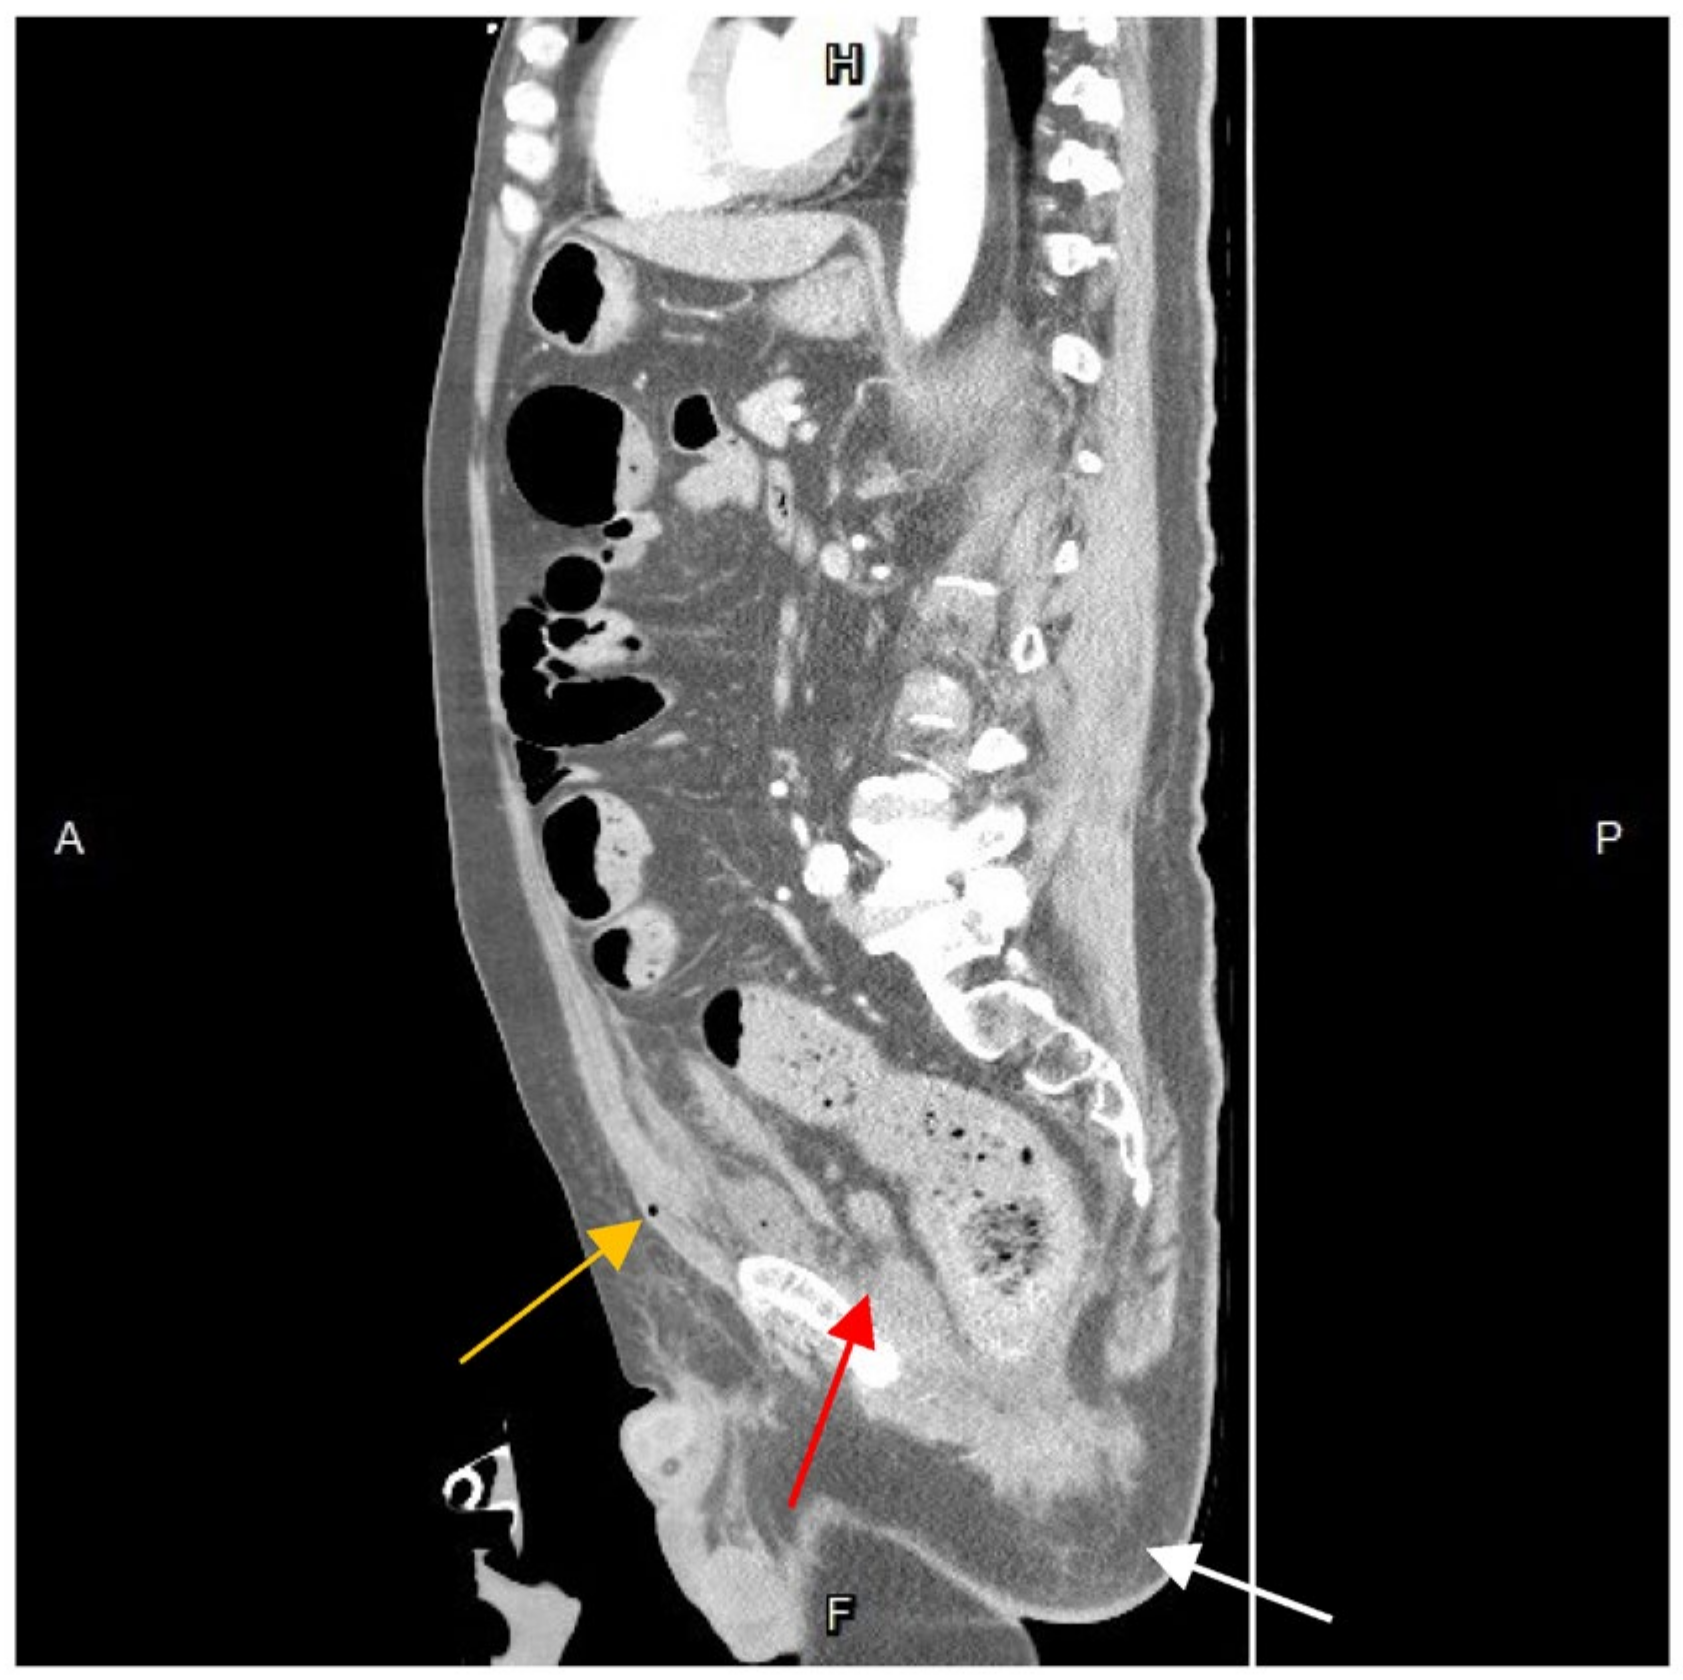

Further diagnostic measures included a plain abdominal radiograph, which showed no pneumoperitoneum or abnormal fluid accumulation. Laboratory findings consisted of an elevated white blood cell count and C-reactive protein level (white blood cells: 27,830/μL; neutrophils: 90.6%; C-reactive protein: 21.65 mg/L). Abdominal contrast-enhanced computed tomography (CT) showed a heterogenous fluid-filled perianal abscess measuring 5.0 × 4.4 × 6.8 cm (Figure 1) in the left perianal region, with extraperitoneal air spreading through the abdominal wall fascia (Figure 2 and Figure 3). The primary abscess was situated in the supra-levator space, potentially involving the levator muscle (infra-levator), as indicated by its migration from the perianal level to the extraperitoneal level. After a comprehensive review of the patient’s symptoms, medical history, age, and current status, immediate arrangements for endoscopic tests, including upper gastrointestinal endoscopy and colonoscopy, were not made. Additionally, gastrointestinal tract specimens, such as fecal samples for calprotectin and lactoferrin, were not collected, thereby not suggesting the likelihood of inflammatory bowel diseases.

Figure 3. Sagittal view of contrast-enhanced computed tomography. The abscess formation seemed to originate in the perianal region (white arrow) and migrate to the supra-levator plane (red arrow) and the preperitoneal space (yellow arrow). With close inspection, the air is spotted extraperitoneal. A, anterior; P, posterior; H, superior; F, inferior.